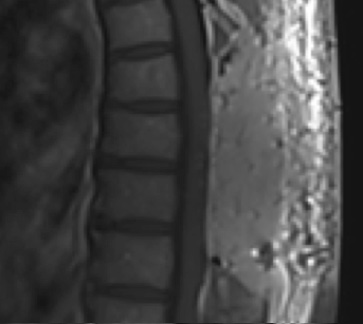

Postoperative MRI T1w demonstrating a gross total resection

Pathology came back as Atypical Meningioma, WHO grade 2. Postoperative MRI showed a gross total resection without residual tumor, and appropriate spinal cord re-expansion. On her most recent follow-up at 6 weeks, she was very pleased with the results from the surgery. She reports resolution of her preoperative thoracic back and radicular pain, and great improvement with her ability to ambulate and overall function. It is demonstrated by her interval VAS of 2/10, and ODI of 23/100. She is expected to continue improving with time and therapy. Follow-up plan is to observe with radiographic surveillance.